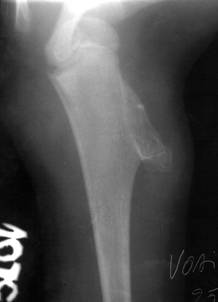

Fig. 79 – Osteocondrom humerus

a)   Osteocondromul (exostoza) – este cea mai frecventa tumora benigna osoasa. Are sediu langa cartilajul de crestere al oaselor lungi ale membrelor, afectand in special exremitatea inferioara a femurului si extremitatea superioara a tibiei. Apare sub forma unei formatiuni pediculate sau sesile cu structura asemanatoare osului spongios, iar continuitatea corticalei si spongioasei tumorii cu cele ale osului din care se dezvolta, constituie un element caracteristic pentru diagnostic. Osteocondromul poate fi solitar, sau multiplu, in acest din urma caz fiind vorba despre o afectiune genotipica ereditara (maladia exostozanta).